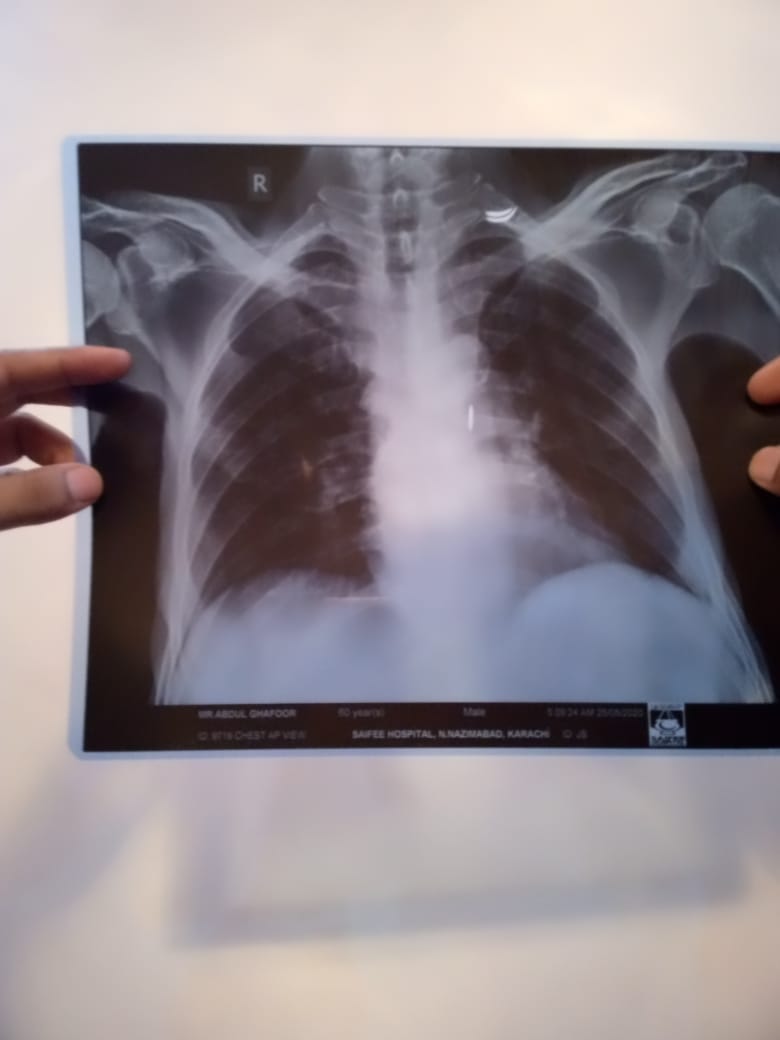

Patient was admitted in hospital due to cancer illness. He didnt have any fever or cough. The doctors performed chest X ray and determined on basis of X ray that patient has contracted coronavirus. I have attached the pictures of the X ray. Please verify if lungs are clear or not.

not necessary that all the patients of cancer have covid 19 but now a days it is nesccery to perform covid test of every immnocompromiz pt. Cancer is one of them . X ray chest is not normal but i m not an xray specialist. All the immunocompromised are nesccery to perform this test and indications to take precautions for doctos . If the test is positive than inform the relatives.